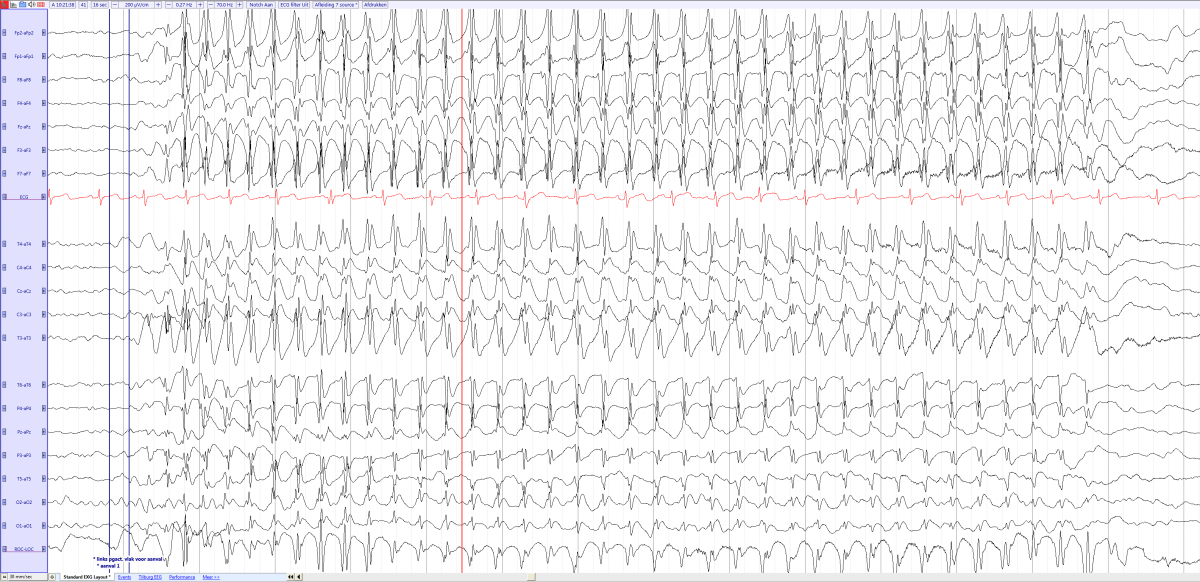

TYPICAL ABSENCE SEIZURE Childhood Absence Epilepsy (CAE) - Petit Mal Epilepsy - Pyknolepsy Childhood Absence Epilepsy | Epilepsy Foundation Frontiers | Absence Seizure Detection Algorithm for Portable EEG Devices | Absence Seizure Eeg